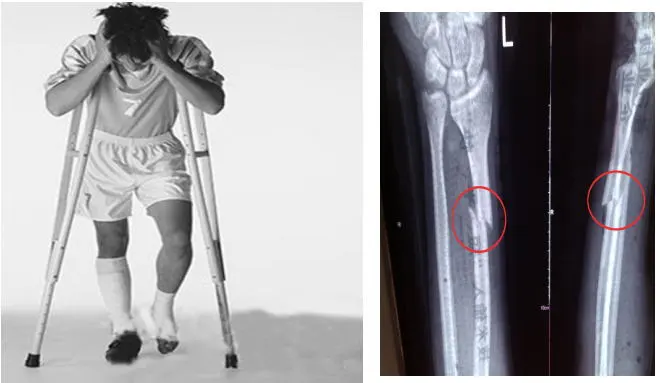

桡骨远端骨折通过“骨02”治疗病例 图源:邵逸夫医院

有个年轻工人的例子很有说服力:他因为外伤,手腕处的桡骨碎得厉害。按传统方法,得开个大口子装钢板,一年后还得再手术。但用了“骨 02”,医生只开了2到3厘米的小口子,把材料注进去,3分钟就固定好了。术后3个月复查,他的骨折愈合得很好,手腕也能正常活动了。